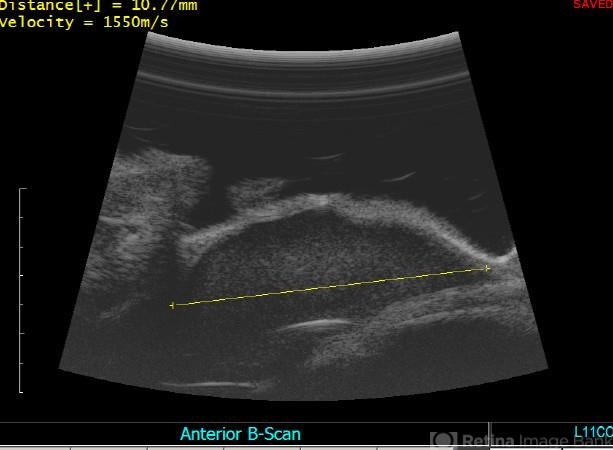

- ciliary body mass, immersion ultrasound, cystic lesion

- Immersion ultrasound of mass shows cystic lesion 11mm in diameter